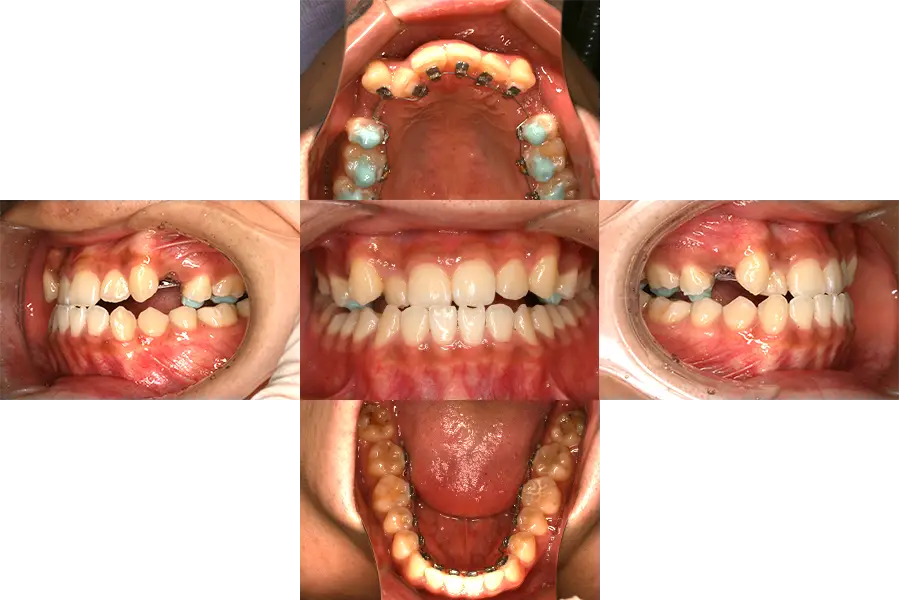

軽度の凸凹の舌側矯正での治療例

- 主訴

- 歯並びが凸凹(叢生)、前歯部に一部反対咬合

- 診断

- 叢生

- 難易度

- リンガル 中等度

- 抜歯の有無

- 無し

- 使用した装置

- 上下拡大装置、舌側ブラケット装置

- 治療期間

- 約1.5~2年

- 費用(税込)

-

基本料金 1,138,500円 調整料(約12~18回) 297,000~396,000円 矯正用アンカー 無し 総額 1,435,500~1,534,500円

- 治療について

治療開始時は、上下歯列弓が狭窄しており、特に前歯部に軽度から中等度の凸凹が認められた。

そのため、始めに拡大装置を使用して歯列弓の側方拡大を行った後に舌側にリンガルブラケットを装着し、凸凹およびかみ合わせを改善した。

- 治療のリスク

違和感、痛み、しゃべりにくさ、虫歯のリスクの増大、歯磨きのしにくさ、ブラケット脱落の可能性。自費診療。